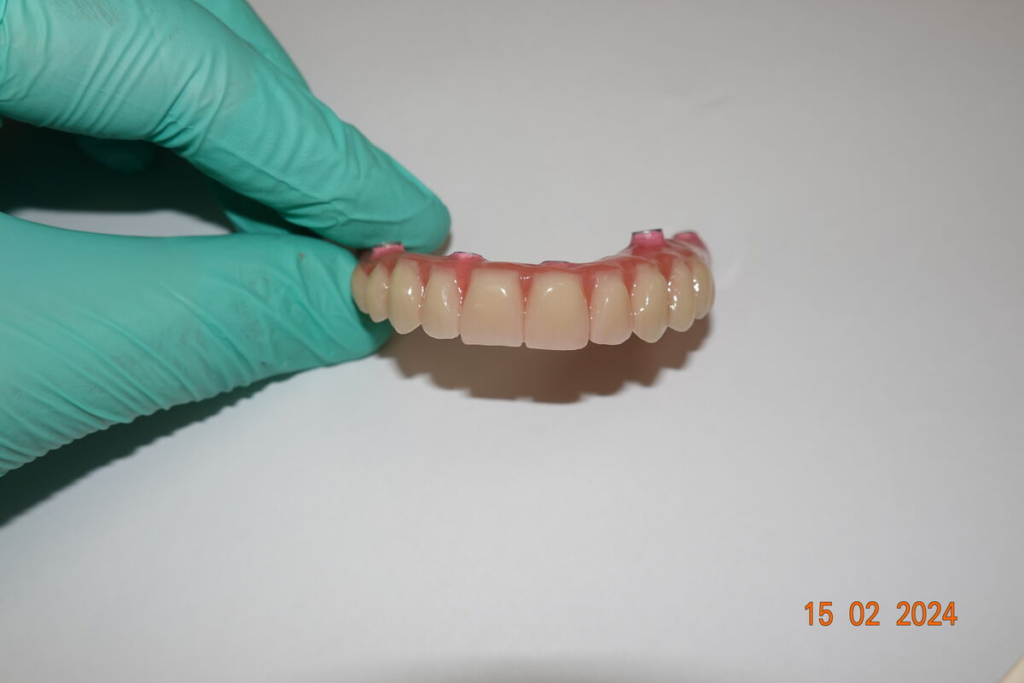

3. Nové zuby tentýž den

Odcházíte s pevnými dočasnými zuby — bez snímatelné protézy.

Můžete mluvit, smát se a jíst měkkou stravu.

Po 4–6 měsících nasazujeme trvalý můstek.

Používáme multivrstvý zirkon pro maximální estetiku, pevnost a dlouhou životnost.

Technika All-on-X — II. fáze